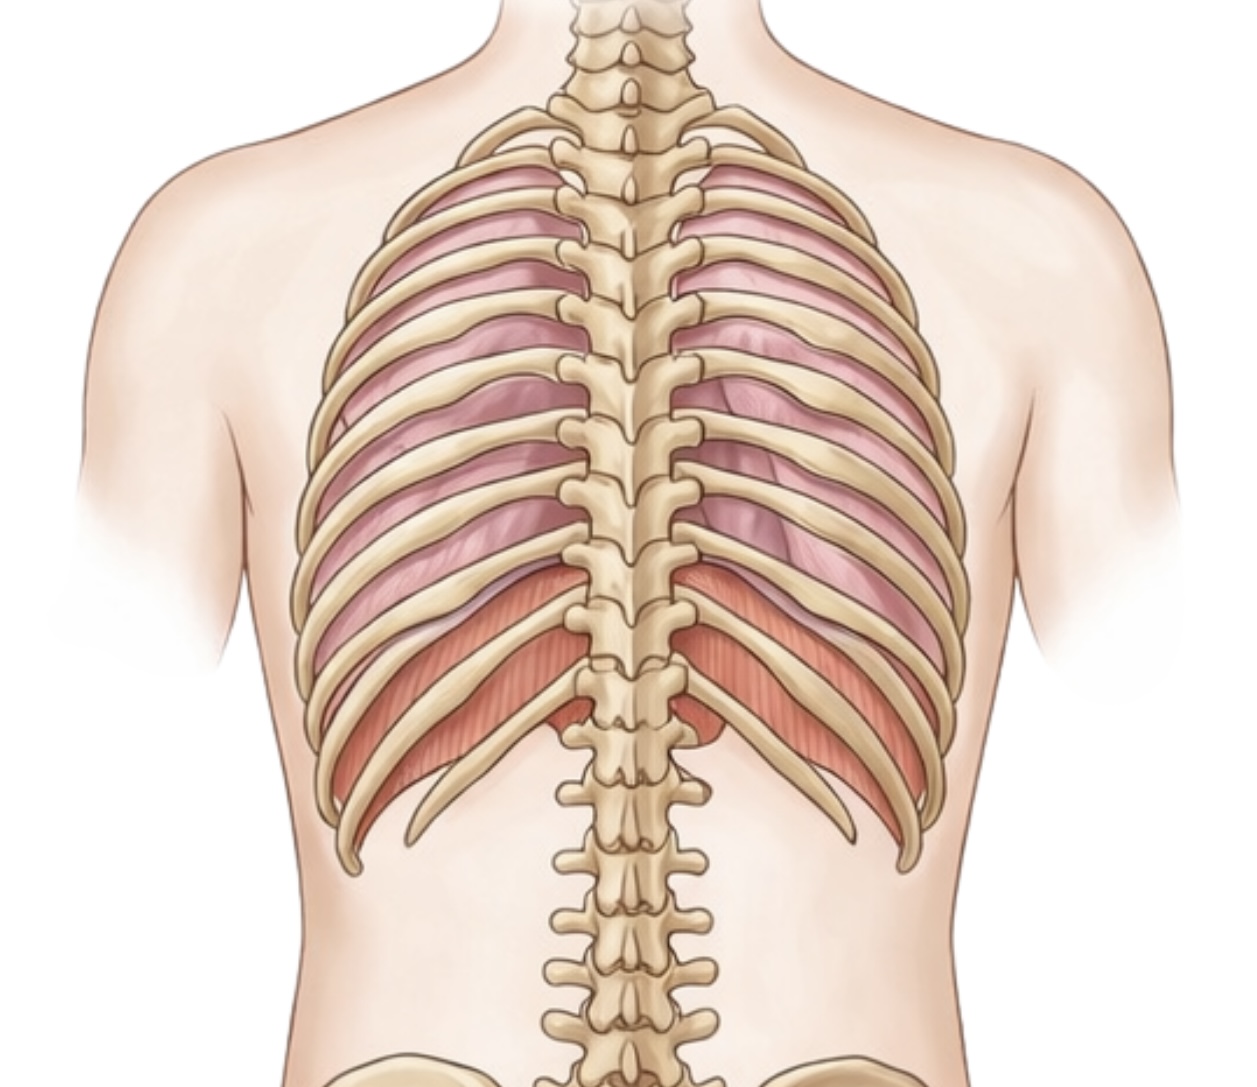

1. 横隔膜:全身を駆動させる「インナーポンプ」の真実

私たちの身体の中には、胸腔と腹腔を隔てるドーム状の筋肉、

横隔膜という名の「生命のエンジン」が眠っています。

その役割は、単に肺に空気を送り込むことだけではありません。

▶️体幹の安定を司る「IAP(腹腔内圧)」の制御塔

正しく深い息を吸う際、横隔膜は力強く下降します。

するとお腹の中に「腹圧」が高まり、

背骨を内側から支える「天然のコルセット」が機能します。

これが、凛とした美しい姿勢の正体です。

▶️現代の子を蝕む「リブフレア」の危機

しかし現代、多くの子どもたちが、

肋骨がパカッと浮いた「リブフレア」という状態にあります。

肋骨が閉じない(リブダウンできない)と、

横隔膜は理想的なドーム形状に戻れず、ポンプ機能が著しく低下します。

その結果、浅い胸式呼吸を余儀なくされ、

身体は常に緊張モード(交感神経優位)に。

「落ち着きがない」「疲れやすい」といったお子さまのサインは、

実は「呼吸の乱れ」が原因かもしれません。